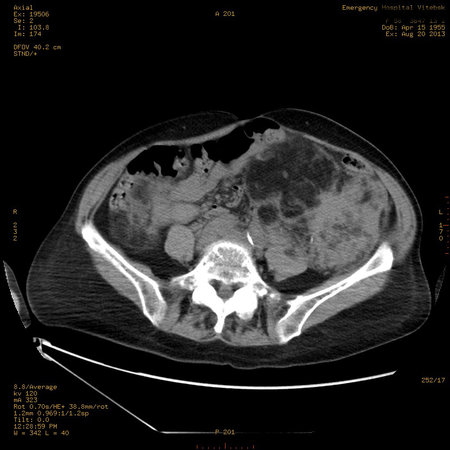

УЗИ почек - туберозный склероз

Пожилая женщина с нормальными мочевиной и креатинином.

Ангиомиолипоматоз почек , думаю компонент туберозного склероза.

Да, туберозный склероз.

Случай консультирован на кафедре радиологии Католического университета г.Лёвен (Бельгия) - зав каф. профессор Р.Оуен.